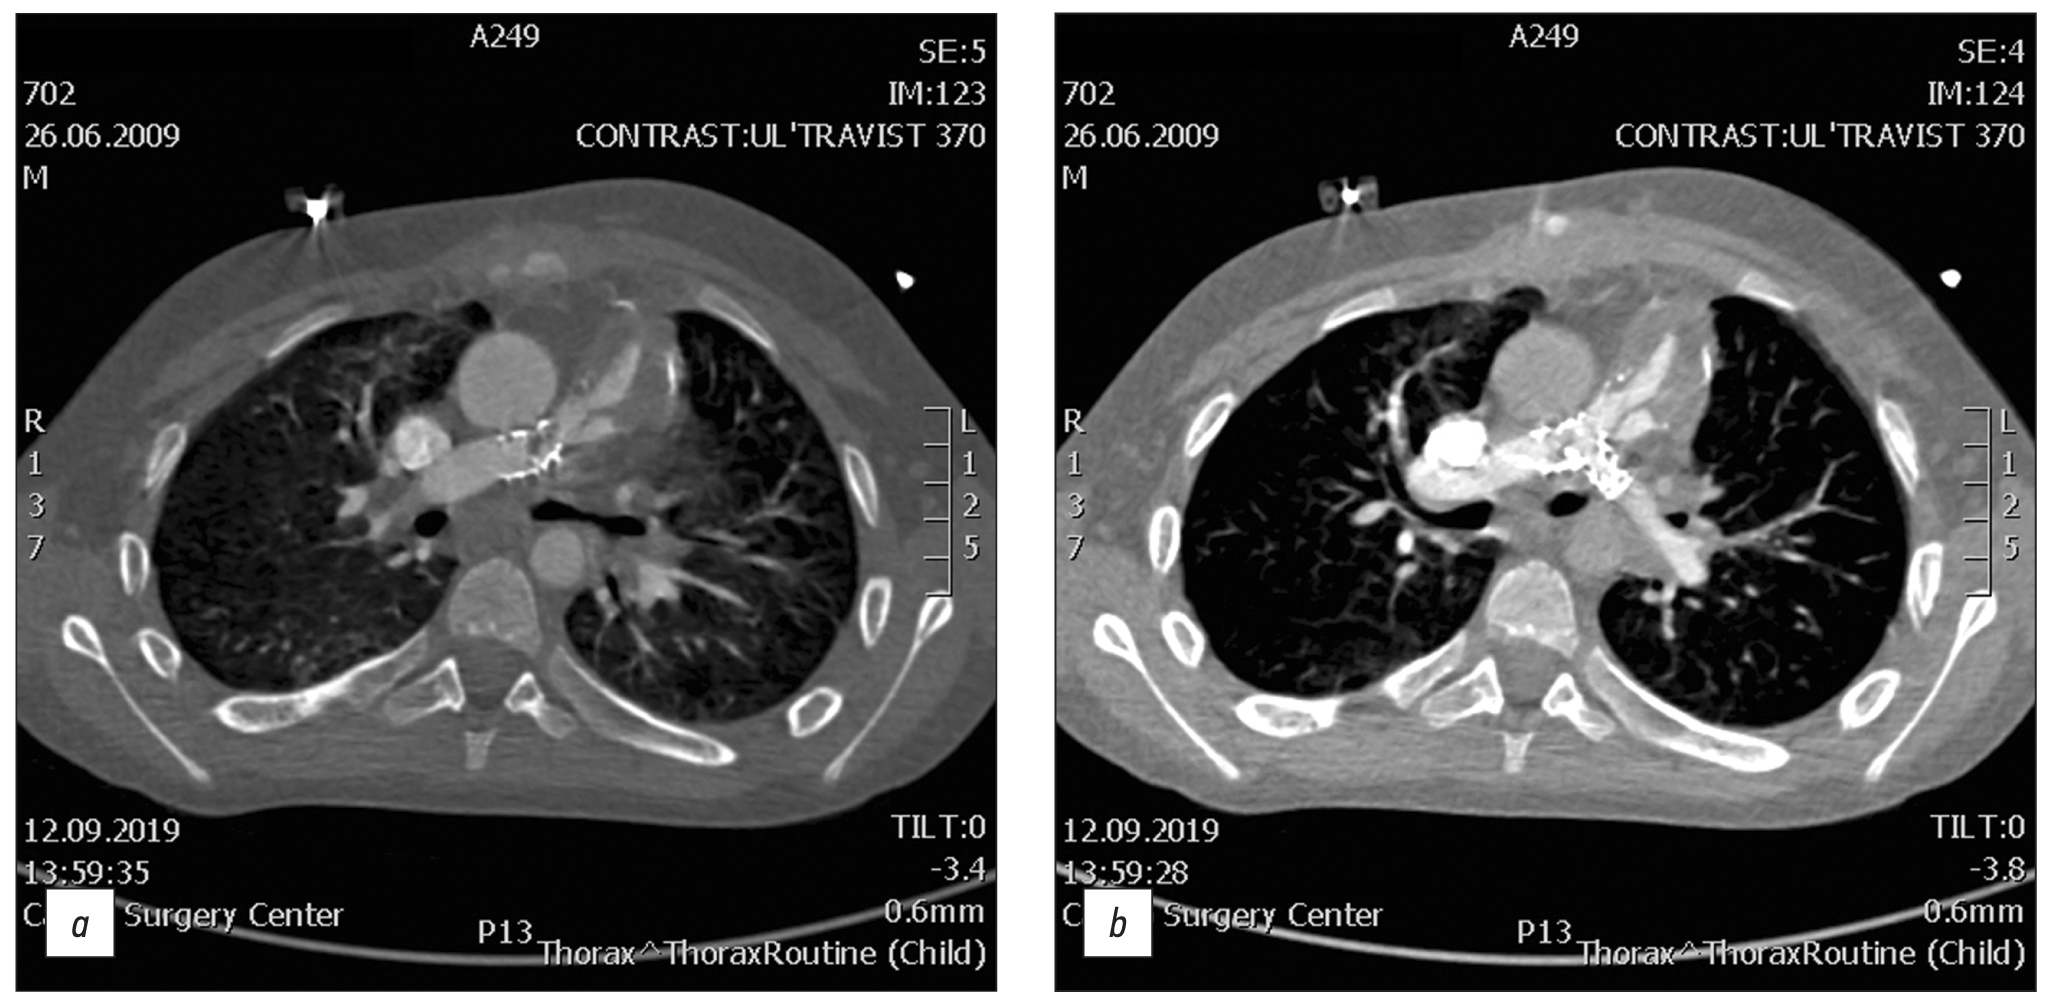

Chronic esophageal fistula as a rare cause of secondary osteomyelitis of the thoracic spine

Abstract

Infectious diseases affecting the spine are inflammatory destructive diseases that involved the organ and its structural elements as a result of infection by hematogenic, lymphogenic, or contact pathways, including may be a complication of surgical intervention. In arriving at an accurate diagnosis, it is extremely important to evaluate the anamnesis, the clinical picture, as well as the data of laboratory studies and radiation diagnostics in the aggregate.

This article presents a clinical case with the development of secondary ThVII–ThVIII vertebral spondylitis due to esophageal fistula. At the initial diagnosis, spondylitis was associated with spinal anesthesia performed six months prior to onset of the disease, as there was a fistulous defect on the skin in the lumbar region. Consequently, surgical interventions were performed three times in a surgical hospital at the place of residence. The data from the endoscopic examination, as well as the patient’s complaints regarding the relationship between meals, the appearance of pain, and the nature of the discharge from the fistula were not taken into account by doctors initially. With the help of an additional examination, including computed tomography of the esophagus with oral contrast and computed tomography fistulography, the main diagnosis was esophageal fistula. Thoracic spondylitis was only a secondary complication.

Thus, the final diagnosis of back pain and fistula in the lumbar region should be formulated after differential diagnosis with alternative diseases of the spine.